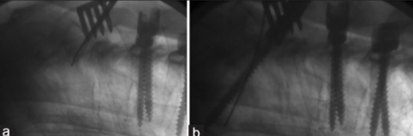

(4)固定棒选择

图8-11 相关文献表明,钴铬合金可提高固定强度及融合率,防止断棒,但也增加了PJK的发生率

(5)内固定方式选择

内固定融合区固定强度过大,如全椎弓根螺钉固定和多棒固定。

融合区内固定强度越坚固,PJK的发生风险越高。

图12 CBT+TT+多棒固定

CBT+TT+多棒固定

从融合节段向活动节段未行过渡性手术,导致局部应力分布不均,局部应力过于集中,也是交界性问题的危险因素之一。

长节段固定时,融合区和活动区应适当行过渡性手术,可降低PJK发生的风险。

图13 长节段全椎弓根螺钉固定,局部应力过于集中